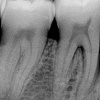

Parodontiit

Parodontiit on mikroobide poolt põhjustatud hammast ümbritsevate kudede põletik, mille tagajärjel hävib hamba kinnituskudede süsteem ja luu, kuni hammas langeb välja. Parodontiidile eelneb alati gingiviit, kuid mitte igast gingiviidist ei...